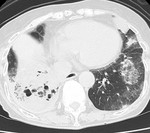

[Weekly Chest Cases]結節性硬化症の肺病変 2011-07-04